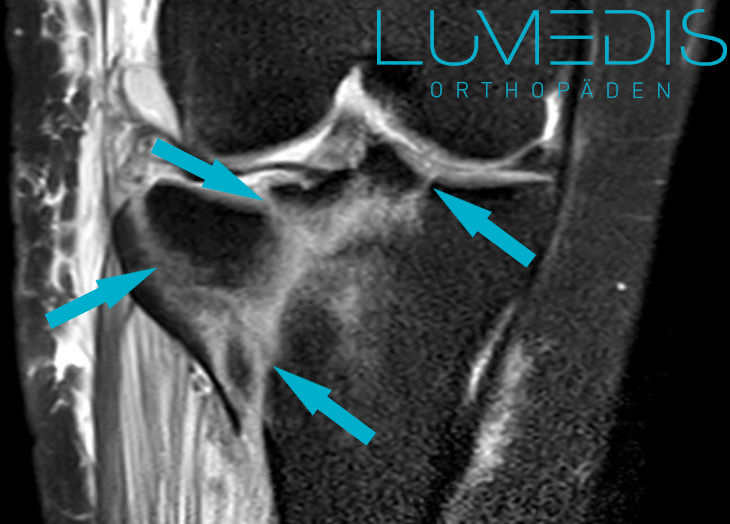

MRT eines Morbus Ahlbäck der medialen Femurkondyle (Innenrolle im Knie)

Unter Osteochondrosis dissecans (OD) versteht man das Absterben von Knochen direkt unterhalb von einer Gelenkfläche ausgelost durch eine lokale Durchblutungsstörung.

Eine Osteochondrosis dissecans löst Schmerzen bei Belastung aus und führt gegebenenfalls zu einer Schwellung.

Typischerweise ist die äußere Seite der inneren Oberschenkelrolle (laterale Seite der medialen Kondyle) betroffen.

Abbildung einer Osteochondrosis diessecans vom Knie